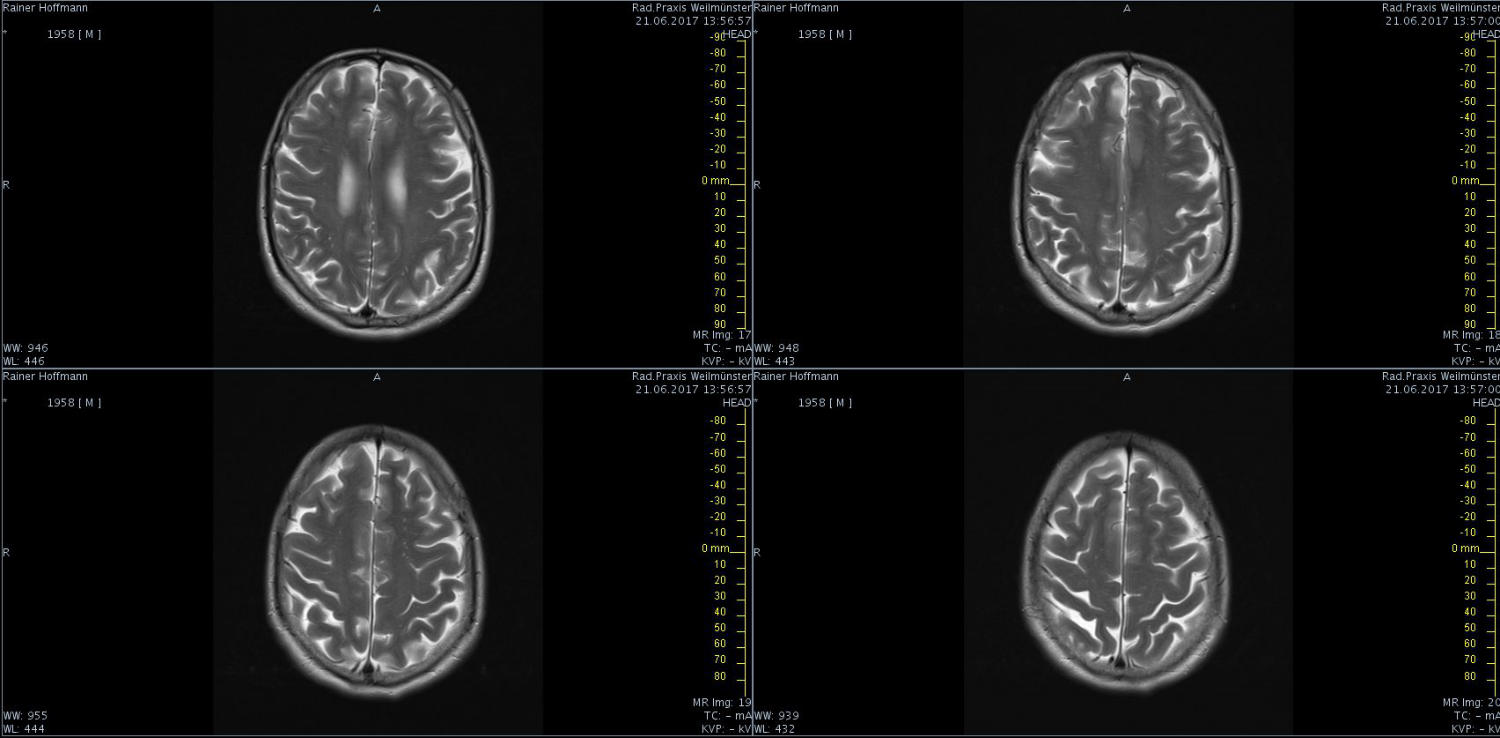

Das ist ja ganz toll, dass Ihr die Seite so schnell gefunden habt. Ich zeige euch jetzt ein ganz, ganz anderes Paßfoto von mir. Es könnte Ähnlichkeiten zu anderen lebenden oder bereits verstorbenen Personen geben. Wenn Ihr das erste Bild oben links anklickt wird es ver- größert dargestellt. Dann kann man mit den Pfeiltasten am unteren Bild- rand durch meinen Kopf blättern. Es gibt nicht viel zu sehen. Vielen Dank an Martina für Ihre Hilfe.

MRT